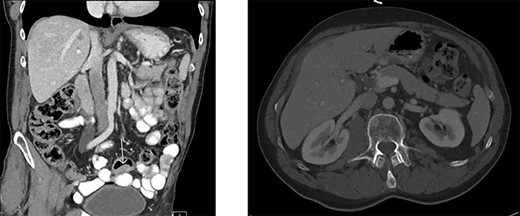

Colonoscopy revealed a polyp in the sigmoid colon and an obstructing tumor suspected for CRC (20 cm from the anal verge) (Fig. 1). An abdominal contrast-enhanced computed tomography showed four lesions in the liver suspected for metastases without lymphadenopathy (Fig. 2). Magnetic resonance of the liver showed five lesions suspected for metastases. Chest X-ray was normal.

Abdominal contrast-enhanced computed tomography. A. Tumor in the sigmoid colon. B. Four hypodense lesions in liver suspected for metastases.